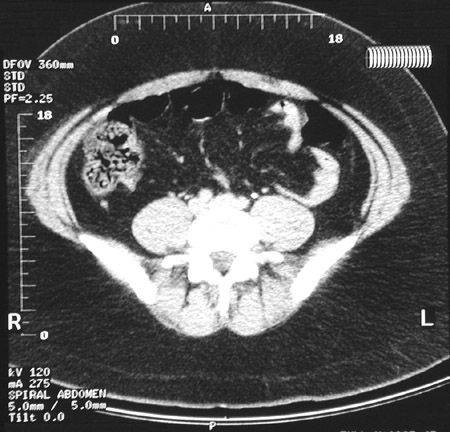

| The patient can hardly fit into the CT scanner to produce this abdominal CT scan. Note the large amount of surrounding adipose tissue with low attenuation. This is morbid obesity, defined as body weight more than 100 pounds (45 kg) over ideal weight. |